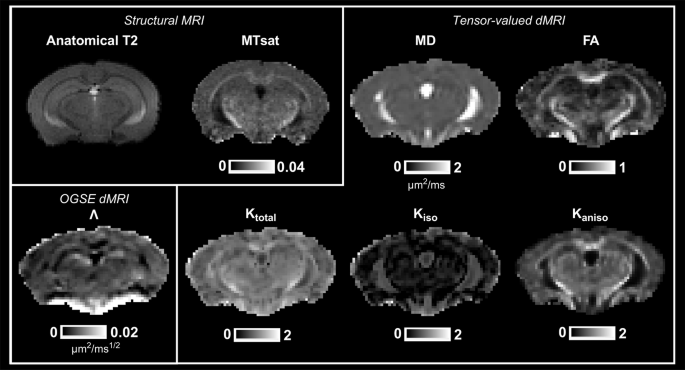

Figure 1 shows representative maps for one mouse at 3 months of age. Kaniso shows enhanced white matter contrast compared to Ktotal, as expected, and Kiso is relatively consistent throughout the brain. \(\Lambda\) shows selective enhancement of distinct regions in the brain with densely packed neurons, such as the dentate gyrus (part of the hippocampal formation).

Structural maps include T2-weighted and MTsat (magnetization transfer saturation). Maps from the OGSE dMRI protocol include \(\Lambda\) (the diffusion dispersion rate). Maps from the tensor-valued dMRI protocol include MD (mean diffusivity), FA (fractional anisotropy), Ktotal (total kurtosis), Kiso (isotropic kurtosis), Kaniso (anisotropic kurtosis).